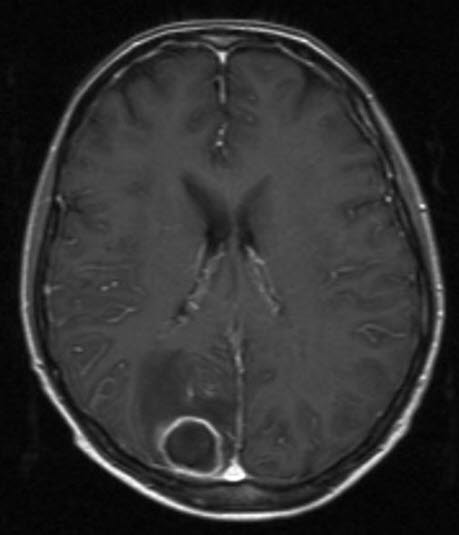

Hjerneabscess, aksialt snitt

Gjengitt med tillatelse av Radiologisk avdeling, Universitetssykehuset Nord-Norge